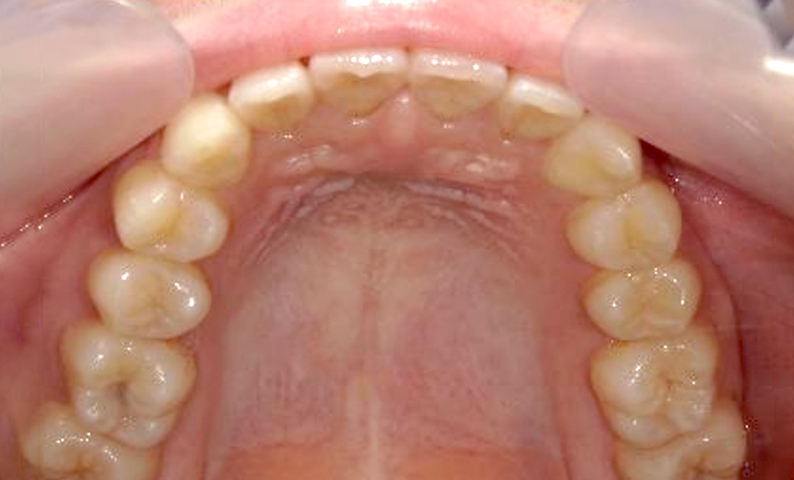

症例:上下顎の部分矯正

症例_002 前歯「捻転歯」症例

治療期間:10ヶ月金額:54万円+税30代女性少しのねじれ捻転歯前歯の突出感

| Before | After |

|---|---|

|